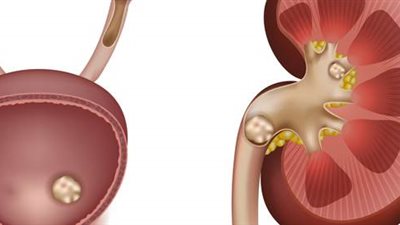

- وهناك أيضًا حدوث الحصوات داخل المثانة نتيجة عدم تفريغ البول بشكل كامل.

وحول أعراض تضيق مجرى البول؟ فهناك أعراض تدل على تضيق مجرى البول أو الإحليل، وهي صعوبة في التبول وذلك نتيجة تضيق المجرى البولي وضعف في قوة دفع البول، مع تخفيف في سمك البول المندفع وأحيانًا تتعدد اتجاهات مجرى البول، وكذلك حدوث حرقة التبول، وعدم الرضا عن تفريغ المثانة البولية والشعور ببول متبقٍ داخل الجسم، وهناك حالات نادرة يشتكي فيها المريض ألما في الخاصرتين نتيجة ضغط البول المتزايد على الحالبين وبالتالي على الكليتين، وهنا يمكن حدوث قصور في عمل الكليتين، وما يسمى بالفشل الكلوي.